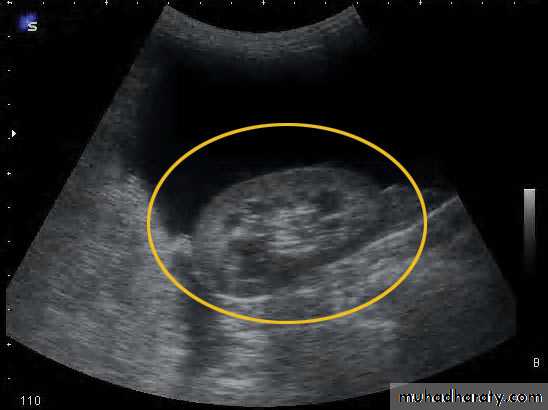

Ultrasound

may reveal a discrepancy in size between the two kidneys.(small size kidney).